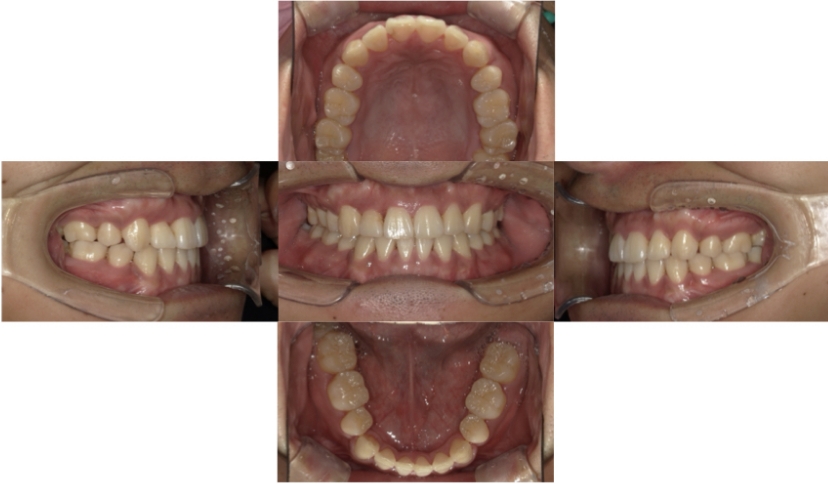

症例1

上顎前突、叢生

抜歯

ブラケット矯正

上下顎叢生、上顎前突(出っ歯、上下の前歯のガタガタ)のケースです。

装置はラビアル(上下表側)で、上顎の小臼歯を2本抜歯を行っています。抜歯したスペースを使って、上の前歯の後方移動と叢生(ガタガタ)と出っ歯の改善を行っています。下は歯と歯の間にIPR(隣接面削合)を行い、スペースを確保し、叢生の改善を行っています。

主訴 前歯のガタガタと出っ歯が気になる。

年齢・性別 47歳 女性

お住まいの地域 神奈川県川崎市

治療方針 抜歯スペースおよびIPRを利用して上前歯の叢生(ガタガタ)の改善

抜歯部位 上顎左右第一小臼歯

使用装置 ラビアル(上下表側)、顎間ゴム

治療期間 2年0か月

治療回数 15回

リテーナー クリアリテーナー

BEFORE

AFTER